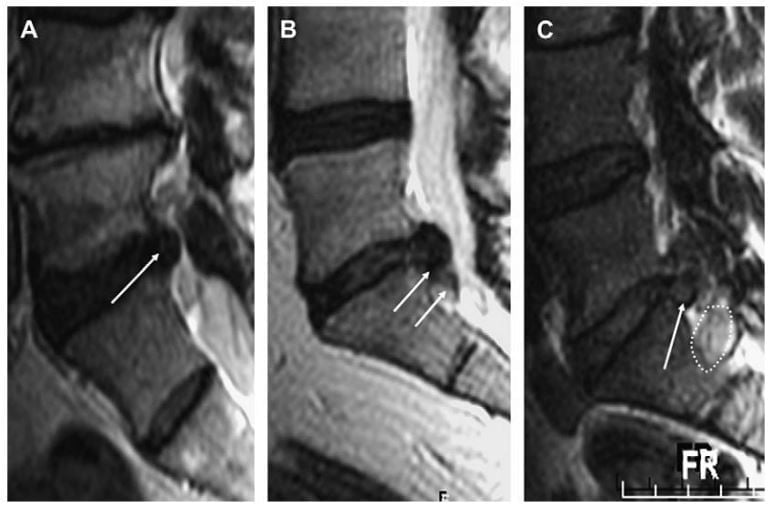

Extrusion có thể phân loại thêm thành mảnh rời hoặc đĩa đệm bị di trú. Đĩa đệm bị di trú là đĩa đệm hoặc mảnh đĩa đệm bị di lệch ra xa khỏi vị trí extrusion nhưngvẫn còn liên tục với đĩa đệm bị extrusion. Mảnh rời là extrusion đĩa đệm bị bong khỏi đĩa đệm gốc (Hình 7). Quan trọng là mô tả mảnh rời, vì đã đệm rời có thể chống chỉ định điều trị xâm lấn tối thiểu như cắt đĩa đệm vi phẫu (microdiskectomie), đốt nhiệt cao tần qua da (RFA), giải ép đĩa đệm cơ học qua da hoặc bơm steroid trong đĩa đệm.

Hình 7. Hình sagittal T2W cột sống thắt lưng minh hoạ protrusion (mũi tên trắng) (A). Gni nhận độ lan theo chiều trên duới không vượt qua bề mặt thân sống trên và duới. Extrusion đĩa đệm có lan chất đĩa đệm xuống dưới vượt qua giới hạn bề mặt trên của S1 (mũi tên trắng) (B). Mảnh đĩa đệm (mảnh rời) cũng nhìn thấy ở phía dưới của phần extrusion (đường chấm trắng).

Hình 10. Hình sagittal T2W (A, B) và sagittal T1W (C) của cột sống thắt lưng chỉ ra nhiều loại thoát vị đĩa đệm khác nhau ở các mức khác nhau. (A) thoát vị đĩa đệm ngang mức L4-L5 có di lệch nhẹ thoát vị xuống dưới (mũi tên trắng); thoát vị này nằm ở mức trên cuống. (B) extrusion đĩa đệm bắt nguồn từ L4-L5 với mảnh thoát vị rời ở mức cuống sống (mũi tên trắng). (C) thoát vị đĩa đệm bắt nguồn từ L4-L5 lan lên trên để nằm ở vị trí dưới cuống (mũi tên trắng). Cuống sống (đầu mũi tên trắng) thấy ngay phía trên của thoát vị.